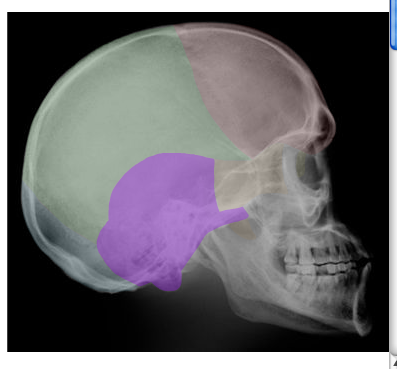

Cranial and Facial Bones

Students will use images and descriptions to reinforce their knowledge of the cranial and facial bones.

A | B |

in blue,  | OCCIPITAL |

| SPHENOID |

in purple,  | TEMPORAL |

in green,  | PARIETAL |